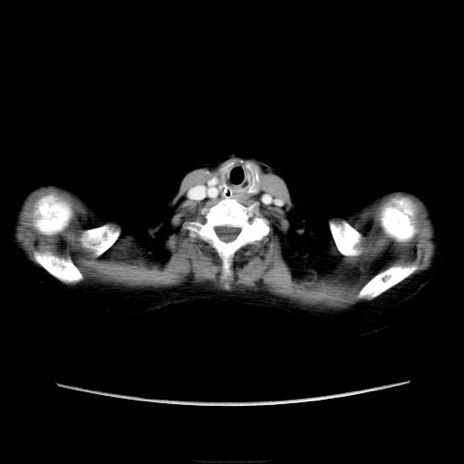

他院CT

横断像